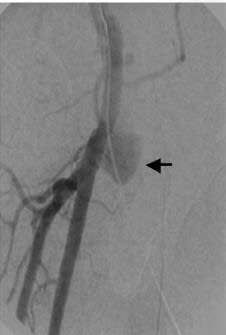

La acumulación casuística después de asistir a más de 20.000 pacientes relacionados con la hemodiálisis (procedimientos en la sala de angiografía, ecografías, mapas vasculares, tratamientos combinados fluoroscopia-ecografía, contrastes alternativos como el CO2, nuevos balones para fístulas - balones cortantes, crioplastia, balón con droga, etcétera), nos animó a plasmar esa experiencia en un libro que pudiera condensar los casos más representativos en la práctica diaria de cualquier radiólogo vascular dedicado al acceso vascular de hemodiálisis. De esta forma, hemos hecho un esfuerzo por imaginarnos a nuestros colegas en su día a día enfrentándose a este campo tan apasionante del vascular intervencionismo. Para ello, hemos planteado este libro con un formato que ayude al especialista a entender cómo tiene que enfocar cada caso desde las esquinas de la clínica, la técnica y el protocolo de actuación; es decir, tal como nosotros mismos venimos haciéndolo diariamente.

Cada caso viene presentado como si fuese una historia clínica, con su motivo de consulta y sus antecedentes personales, especialmente los referidos a los accesos vasculares de hemodiálisis, seguido de una exploración física. Se acompaña de un informe del procedimiento realizado con la técnica empleada y los abordajes, así como los balones de angioplastia y/o stents utilizados. Para finalizar, escribimos unos comentarios sobre el procedimiento realizado y todo caso va acompañado de un gran número de imágenes explicativas de alta calidad